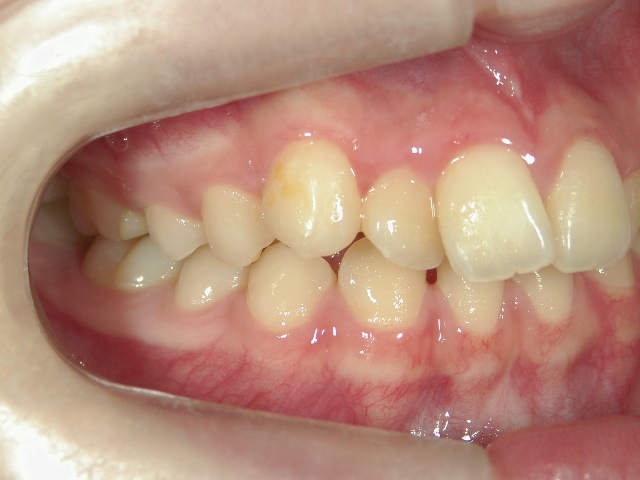

矯正歯科 治療前 右

矯正歯科 治療前 左